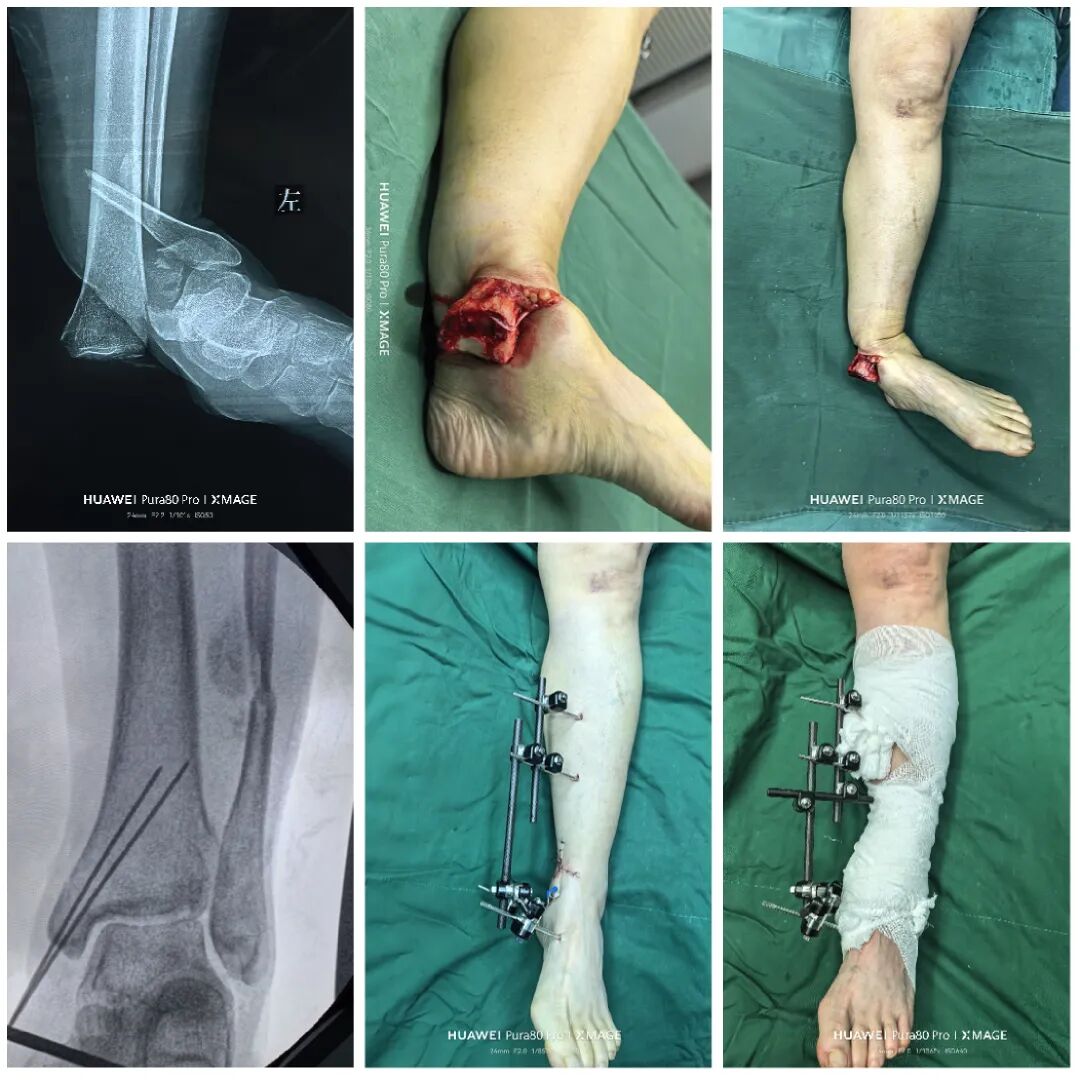

术后1周

内侧伤口愈合良好

行二次确定性手术

缝合前侧和后外侧切口

取外架

缝合钉道

踝关节被动活动良好

期待切口和功能的恢复